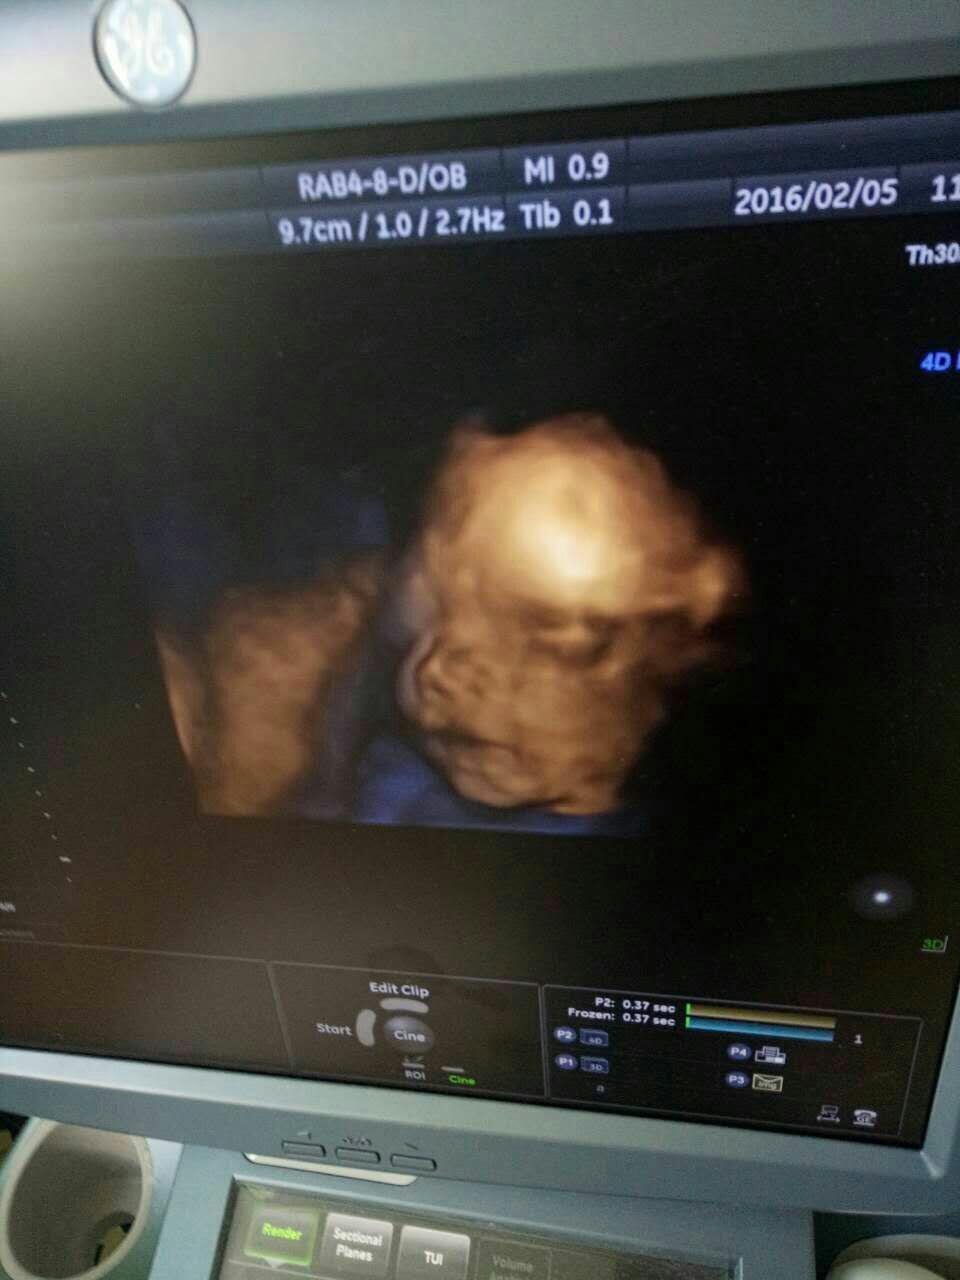

宝宝9岁7个月19天 LV.4

宝宝9岁8个月6天 LV.8应该是男孩

孕40周+0天 LV.4男的,胎心率高

宝宝9岁5个月12天 LV.1男宝,胎心160以下是男宝

宝宝9岁7个月15天 LV.9胎心150以下是男宝吧,还说双顶径减去股骨大于2是男宝

宝宝9岁7个月15天 LV.9所以我觉得是女宝啊,而且胎心大于150

2个宝宝 LV.9女宝吧,正常是120-160,160以上就不正常了,我女儿那时就是150左右

宝宝9岁7个月15天 LV.9我说的胎心150以下是男宝,双顶径大于2是男宝,她两个都不符合,不就是女宝?

宝宝9岁7个月5天 LV.7女孩胎心率快,一般都在150以上,男孩一般都在150以下,我一胎是女儿,胎心一直都在150以上,这个是二胎,多半又是女儿,胎心还是150以上,我多希望肚子这个是男孩!